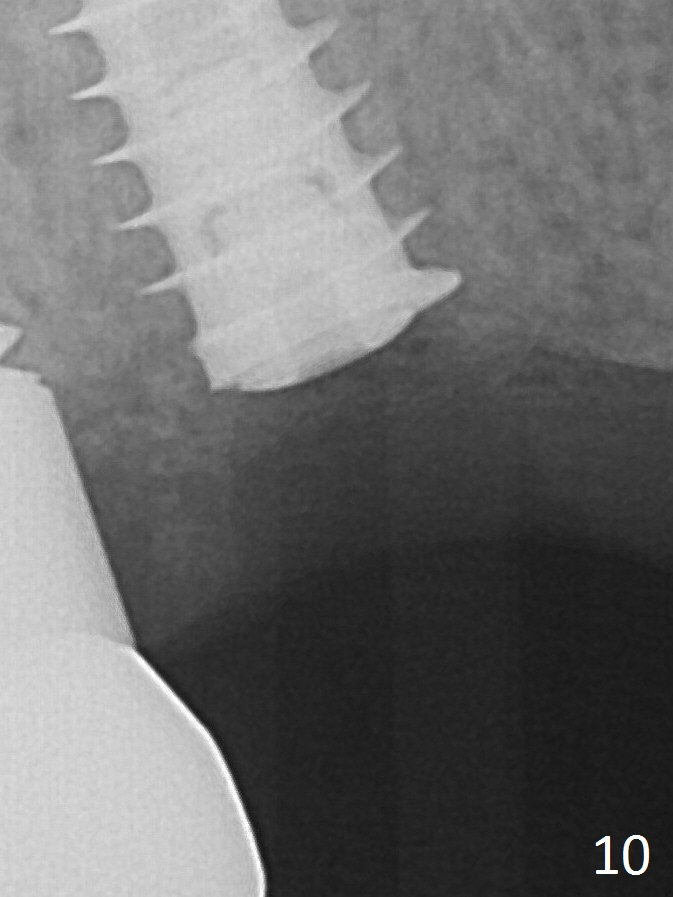

There is mild crestal bone loss 3.5 months postop (Fig.10).